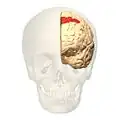

Image of brain with Brodmann area 8 shown in red | |